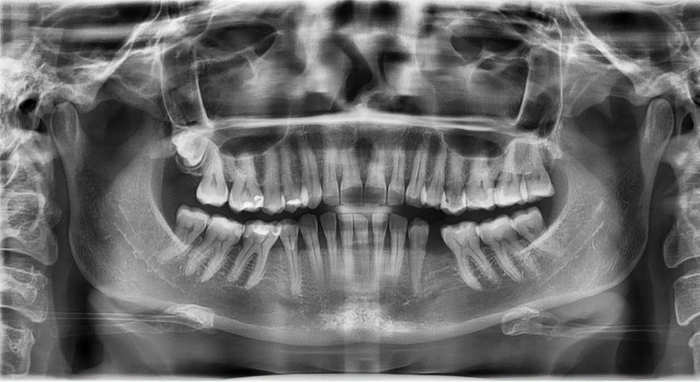

21 ) Ортопантомография (только для детей и льготной категории населения в целях зубопротезирования)

Это панорамный двухмерный снимок, на котором видны все зубы.